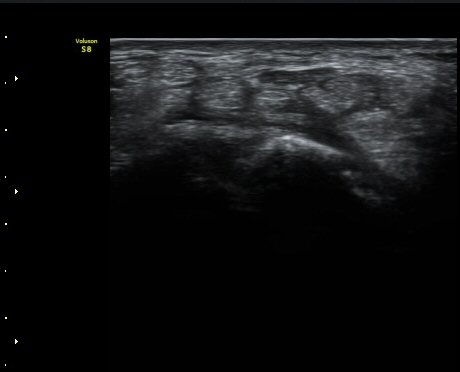

ŽÃËÀÚ¸¦ Á¶±Ý ´õ ¸»´ÜÀ¸·Î À̵¿ÇÏ´Ï Á¤Áß½Å°æ ½ÉºÎ¿¡ Àú¿¡ÄÚ ³¶Á¾ÀÌ °üÂûµÇ°í(»çÁø 4),

³¶Á¾ÀÌ Á¤Áß½Å°æ ¼öÁö °¡Áö¸¦ ¾Ð¹ÚÇÏ´Â ¸ð½ÀÀÌ °üÂûµÈ´Ù(»çÁø 5, 6, 7).